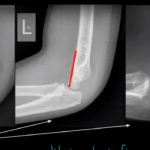

Interpretation of Elbow X-rays

Courtesy: Anna Pickens MD emin5.com